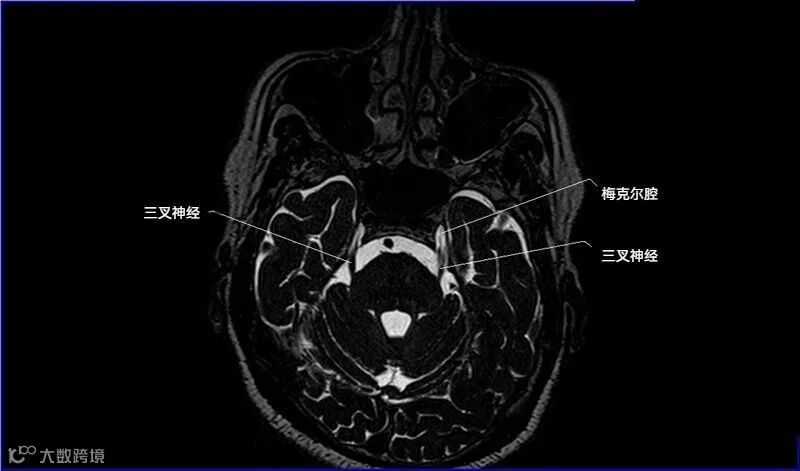

一嗅二视三动眼,四滑五叉六外展,

七面八听九舌咽,迷走及副舌下全。